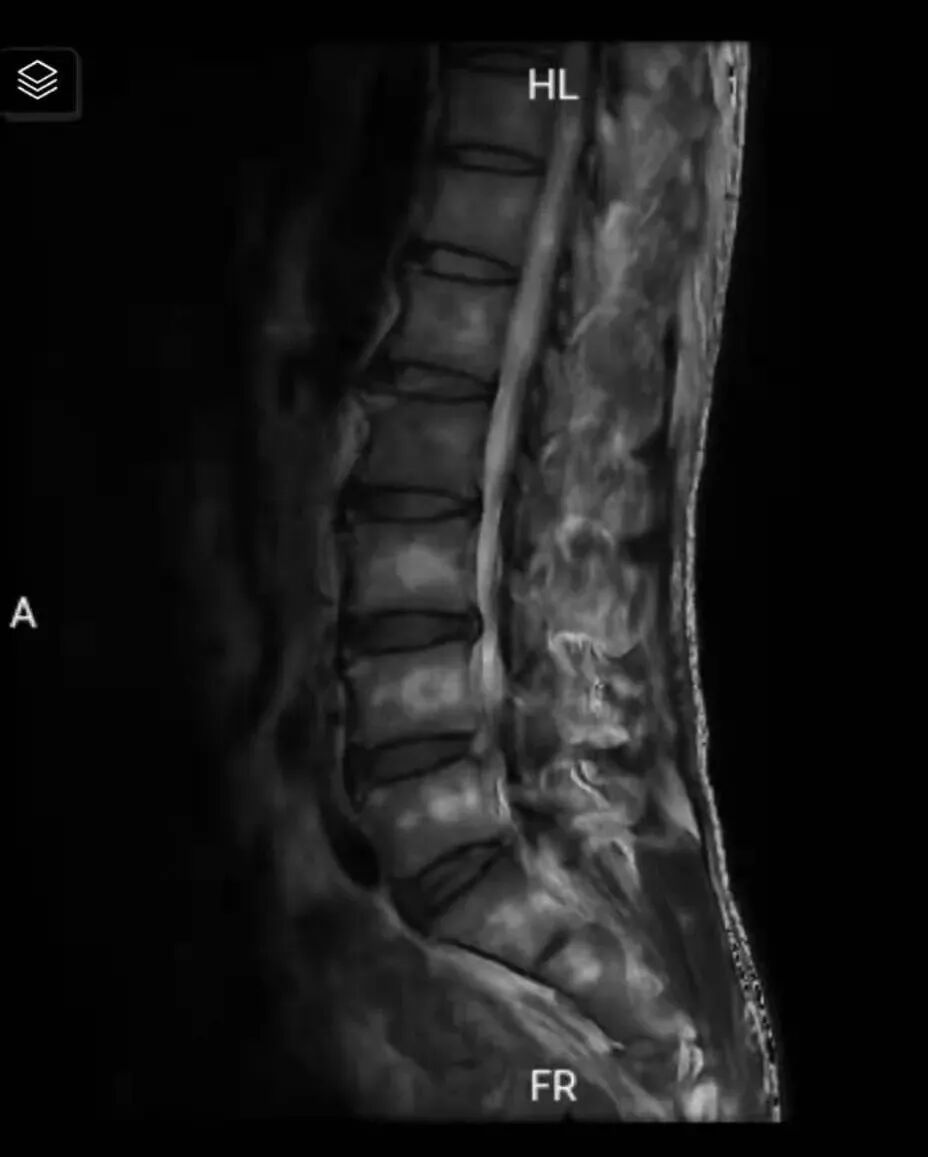

术中视野图